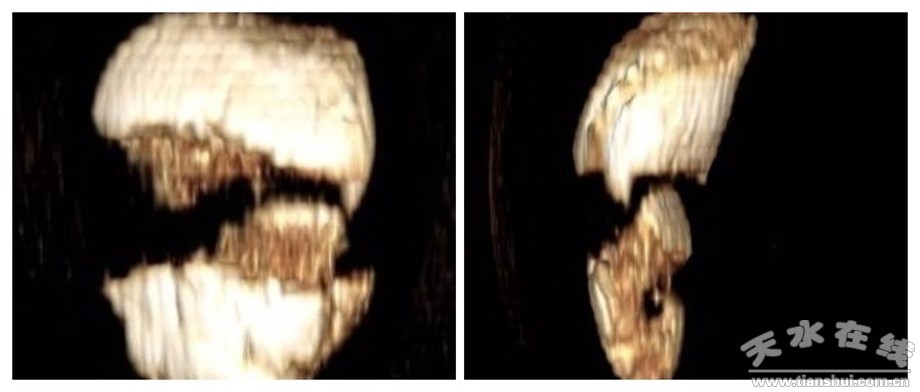

患者收住市一院运动医学科后,进一步完善三维CT,检查提示“髌骨下极存在多个大小不一的碎骨块,骨折线累及髌骨下1/3关节面”。